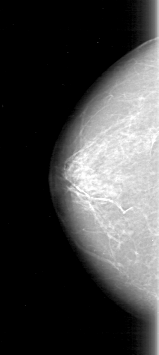

D_4097_1.LEFT_MLO

FILE: D_4097_1.LEFT_CC.OVERLAY

TOTAL_ABNORMALITIES 1

ABNORMALITY 1

LESION_TYPE MASS SHAPE IRREGULAR MARGINS ILL_DEFINED

ASSESSMENT 2

SUBTLETY 3

PATHOLOGY BENIGN

TOTAL_OUTLINES 1

BOUNDARY